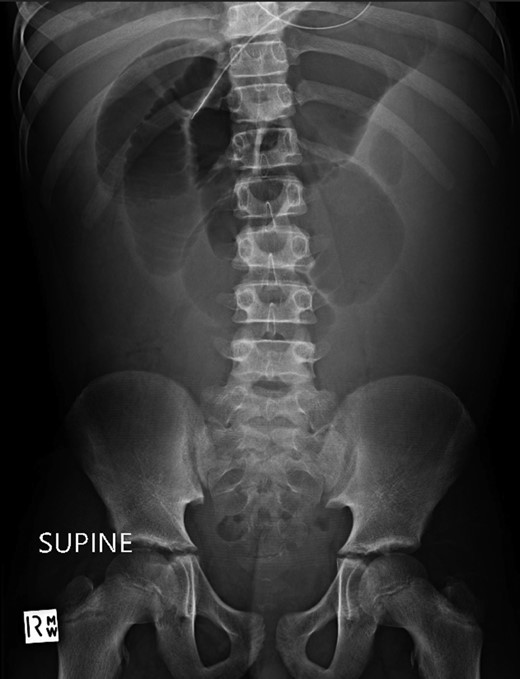

A 10-year-old boy presented unwell with generalized peritonitis after 3 days of abdominal pain, nausea and anorexia. He had a low-grade fever but all other vitals were within normal limits. Blood tests showed a raised white cell count of 16 × 109 with neutrophilia and raised C-Reactive Protein of 127 mg/l. Laparoscopy revealed generalized purulent peritonitis secondary to perforated appendicitis. Appendicectomy was performed and the appendiceal stump was secured. Lavage of the abdomen was performed with a minimum of four litres of warmed normal saline. Fluid was suctioned, an abdominal drain was placed and the pneumoperitoneum was deflated. By the second postoperative day, he developed an ileus with persistent vomiting (Fig. 1). This was managed conservatively with nasogastric intubation, bowel rest, electrolyte replacement and fluid therapy. It became clear by the fifth postoperative day that the patient had intestinal obstruction. On examination, he had a distended abdomen, with intractable nausea and vomiting. Blood tests revealed a normal white cell count and potassium remained at 3.3 despite supplemental intravenous replacement. Abdominal X-ray revealed a small bowel obstruction and he was taken back to theatre for an emergency laparotomy (Figs 2 and 3). A small bowel volvulus was discovered, with no evidence of intestinal malrotation. The volvulus involved a segment of distal jejunum to proximal ileum causing complete small bowel obstruction.

Supine abdominal radiograph on day 5 showing dilated small bowel loops with no bowel gas evident in the colon.